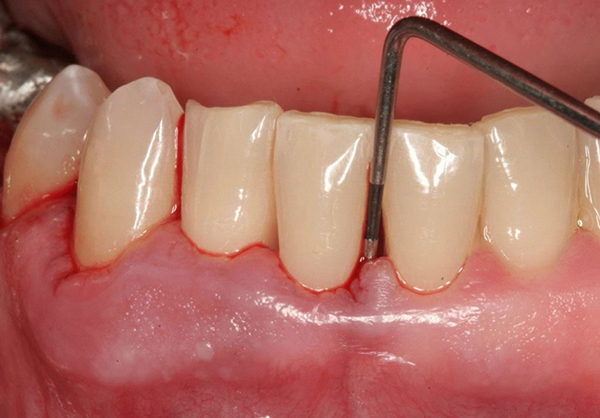

Фото 1. Стоматолог проверяет оголяются ли корни и шейка зубов у пациента, страдающего пародонтозом, при помощи зонда.